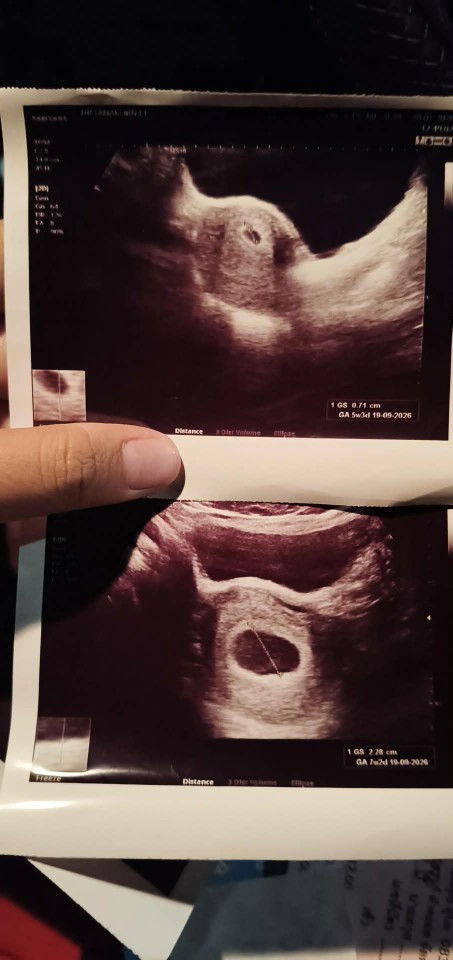

เมื่อวานไปหาหมอซาวด์ท้องเห็นไม่ชัดคุณหมอเลยใช่วิธีสอด เห็นชัด ได้ยินเสียงหัวใจ 6สัปดาห์ ได้ยาบำรุงเลือดมาทานหลังจากกลับเราไปเดินห้างต่อปรากฏว่าเลือดออกเยอะมากต้องใส่ผ้าอนามัยเปลี่ยนไป2แผ่น แผ่นที่3เช้ามา ก็ยังมีเลือดแต่ไม่เยอะเท่าเมื่อวาน ท้องแรกจิตใจกังวลกลัวไปหมด ตอนนี้ใส่แผ่นที่4 ถ้าหยุดไหลก็พอให้สบายใจถ้าไม่หยุดไหลต้องไปโรงพยาบาล แม่ๆท่านไหนเป้นไหมคะ น้องจะเป้นอะไรไหม หรือเพราะเราเดินเยอะ🥺🥺 #ขอบคณสำหรับคำตอบล่วงหน้านะคะ #ท้องแรก #คอมเม้นท์มาหน่อยคะ